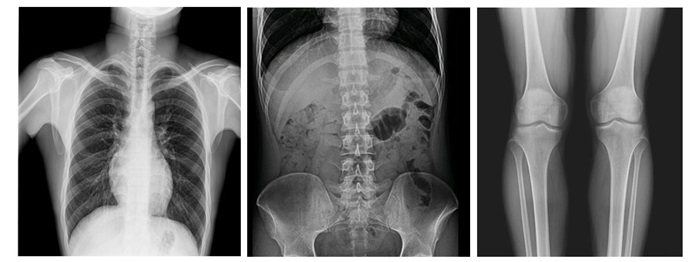

采用新一代動態(tài)平板探測器,兼具動靜態(tài)采集功能,輕松實現(xiàn)數(shù)字攝影、數(shù)字胃腸、數(shù)字透視、數(shù)字造影、實時高清點片、視頻保存和回放等功能,滿足多科室臨床檢查需求。

17×17英寸大幅面成像,一次曝光即可實現(xiàn)胸部、腹部全覆蓋,無需移動即可觀察整個動態(tài)過程,避免拖尾、噪聲對圖像的影響,避免漏診誤診;最高30幀/s采集幀率,動態(tài)影像更流暢,便于使醫(yī)生觀察細微病變,提高診斷的準確性。